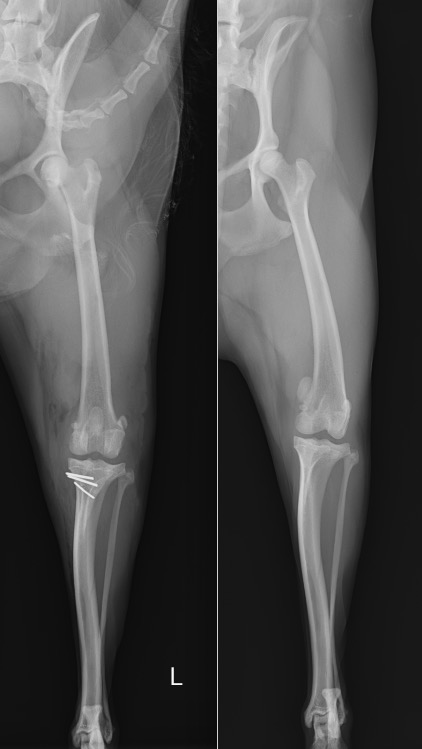

X線を見ると、膝蓋骨が本来あるべき位置(赤点線)から内側に脱臼してしまっていることが分かります。(黄色)

整形外科学的検査とX線検査により、左右共に膝蓋骨内方脱臼のGrade3と診断しました。

重症度としては4段階中3番目であり、日常的に脱臼している状態と推察されました。

術前・術後のX線を見比べると、膝蓋骨が真ん中に整復されていることが分かります。

左後肢 【左:術後 / 右:術前】